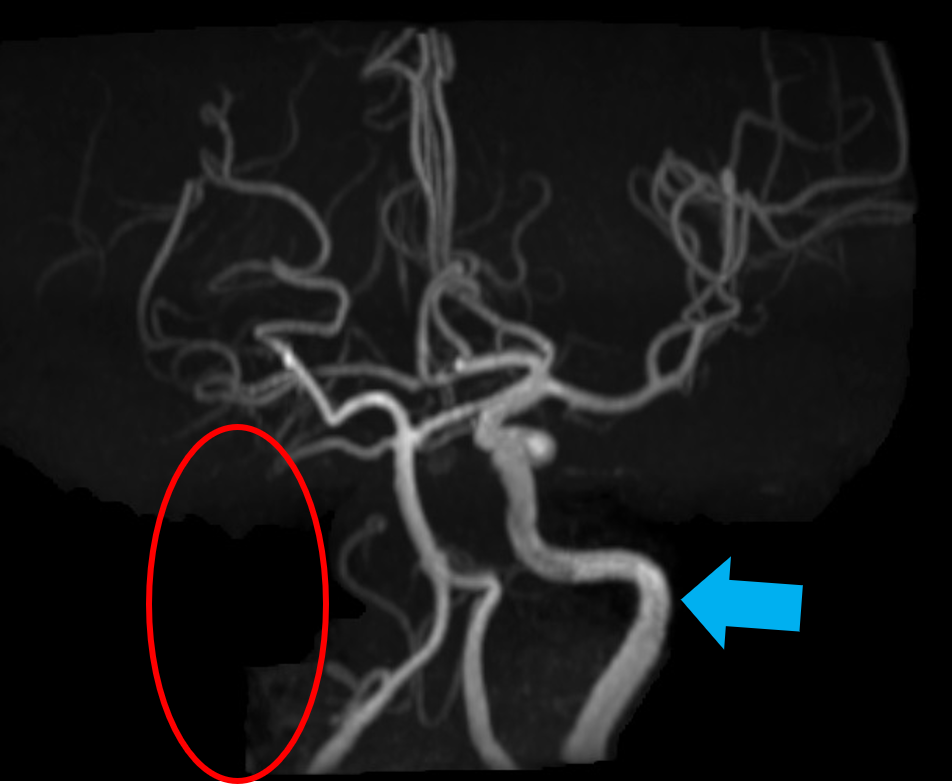

●脳流血シンチグラフィ

脳流血シンチグラフィは、脳にある血管の血流量を調べる検査です。脳流血を反映する薬剤を投与し、脳血流が豊富なところを赤色で、血流が乏しくなっているところを青色で表示して画像化します。

下に提示した症例は、脳梗塞を発症した患者さんの、核医学とMRI画像です。左図の脳血流シンチグラフィ画像では、画像左側が緑や青色で表示され、脳血流が低下していることが分かります。中央の画像では、脳血流が低下しているところが白く描出され、右図の脳血管を描出したMRI画像では左の脳動脈は描出(青矢印)されていますが、右の脳動脈は描出されていません(赤丸)。